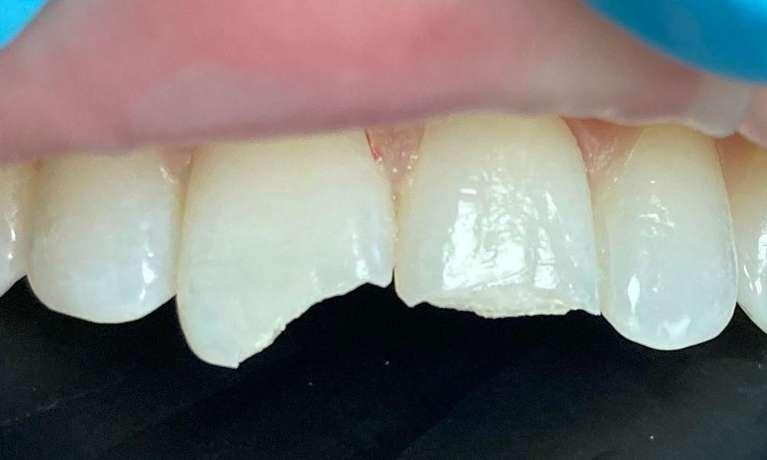

After this tooth was chipped, we placed composite bonding with the aid of our Solea Laser! This procedure used no shots or drills and there was no removal of tooth structure!